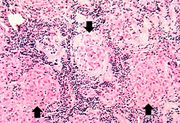

| 03:47, 19 August 2013 | IPLab3ForeignBodyGranuloma2.jpg (file) | 74 KB | Seung Park | This higher-power photomicrograph demonstrates the small focal cellular lesions (arrows) found throughout the parenchyma of the lung. | 1 | |